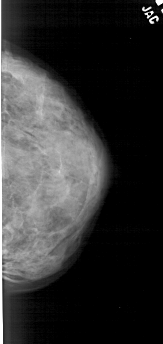

A_1684_1.RIGHT_MLO

RIGHT_MLO LINES 5311 PIXELS_PER_LINE 2461 BITS_PER_PIXEL 12 RESOLUTION 43.5 NON_OVERLAY